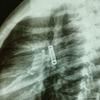

Um grupo de médicos do Hospital Imam Khomeini, na cidade de Ahvaz, no Irã, perto da fronteira com o Iraque, extraíram 452 pequenos objetos de metal do estômago de um homem de 36 anos. Aproximadamente 2,9 kg de parafusos, porcas de metal, chaves, placas e outras peças, bem como pedras, foram encontrados no corpo do paciente, que apresentou queixas de dor abdominal crônica, vômitos frequentes e intolerância a líquidos e alimentos, devido à obstrução da saída gástrica, segundo revelaram uma radiografia e uma endoscopia. As informações foram publicadas em artigo no Journal of Medical Case Reports.

De acordo com as informações, os médicos levaram o homem para a cirurgia e, por meio de uma incisão em seu estômago, extraíram os objetos. Os acompanhantes do paciente mencionaram um histórico de ingestão gradual de peças metálicas até três meses antes da ida ao hospital. O paciente estava consciente e apresentava sinais vitais estáveis.

Cinco dias após a operação, o homem foi transferido para o serviço de psiquiatria em boas condições gerais e foi diagnosticado com psicose. Segundo o artigo, seu quadro voltou ao normal no acompanhamento.

Os médicos observaram que ele era fortemente viciado em ópio - substância produzida a partir da papoula que provoca efeitos no corpo, como sensação de relaxamento e alucinações leves, podendo levar à dependência caso seja usada regularmente. Apesar da grande quantidade de metal consumida, o homem aparentemente não sofreu nenhum efeito colateral antes de sua primeira internação hospitalar por esse problema. Testes posteriores também revelaram que nenhum objeto metálico havia entrado em outras partes do seu sistema digestivo.